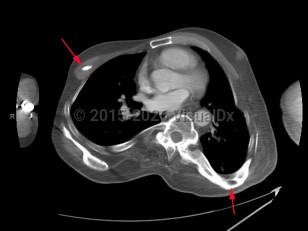

Progressive osseous heteroplasia in Adult

A rare autosomal dominant disorder. Initial manifestation is primary osteoma cutis, a condition of true bone formation within the skin, usually beginning in infancy. Lesions are tender and may ulcerate. Progresses to involve bone formation in deep connective tissue and skeletal muscle. May result in restricted movement and abnormal growth.